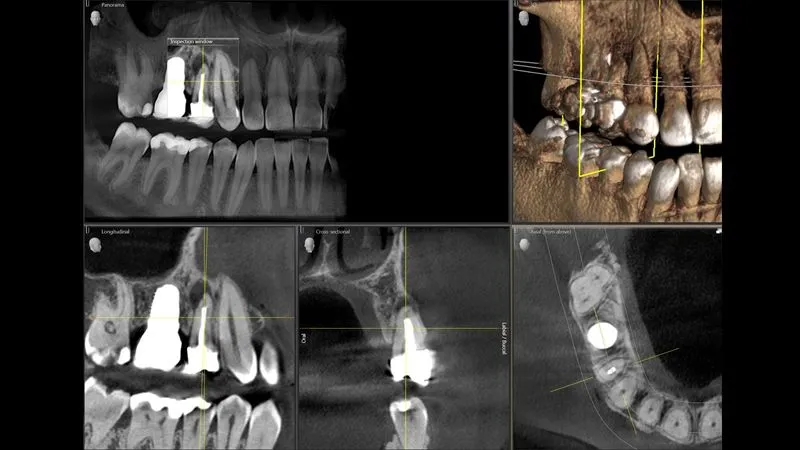

- Izvanredne slike: Jedinstveni DCS senzor za najbolju kvalitetu slike

- Pouzdane oštre slike: Tehnologija Sharp Layer nudi mogućnost prikazivanja pouzdane oštrine na različitim razinama

- 3D prema vašim potrebama: Pomoću funkcije Low Dose i HD možete stvarati 3D slike u rasponu doza 2D rendgenskih i HD slika rezolucije do 80 μm